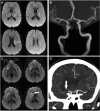

Stroke is the leading cause of disability in the USA and a major cause of mortality worldwide. One out of four strokes is recurrent. Secondary stroke prevention starts with deciphering the most likely stroke mechanism. In general, one of the main goals in stroke reduction is to control vascular risk factors such as hypertension, diabetes, dyslipidemia, and smoking cessation. Changes in lifestyle like a healthy diet and aerobic exercise are also recommended strategies. In the case of cardioembolism due to atrial fibrillation, mechanical valves, or cardiac thrombus, anticoagulation is the mainstay of therapy. The role of anticoagulation is less evident in the case of bioprosthetic valves, patent foramen ovale, and dilated cardiomyopathy with low ejection fraction. Strokes due to larger artery atherosclerosis account for approximately a third of all strokes. In the case of symptomatic extracranial carotid stenosis, surgical intervention as close as possible in time to the index event seems highly beneficial. In the case of intracranial large artery atherosclerosis, the best medical therapy consists of antiplatelets, high-dose statins, aggressive controls of vascular risk factors, and lifestyle modifications, with no role for intracranial arterial stenting or angioplasty. For patients with small artery occlusion (ie, lacunar stroke), the therapy is similar to that used in patients with intracranial large artery atherosclerosis. Despite the constant new evidence on how to best treat patients who have suffered a stroke, the risk of stroke recurrence remains unacceptably high, thus evidencing the need for novel therapies.